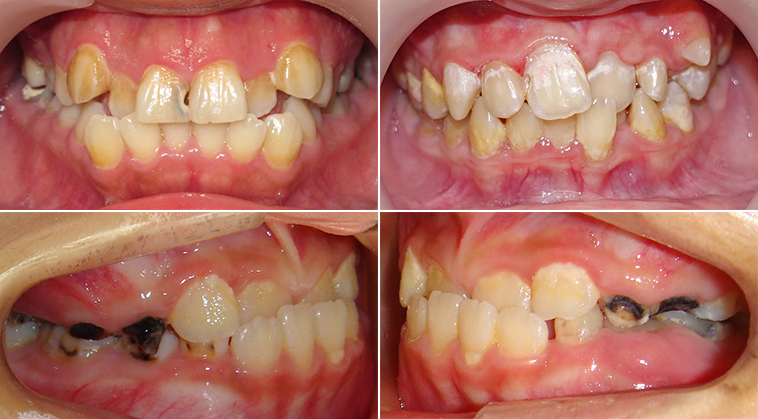

齒列不整的牙齒經常存有食物堆積的死角,而存有食物堆積的死角的牙齒則易造成清潔不易,牙齒清潔不易會促使牙齒產生牙結石與牙周病 (圖4)。

(圖4)齒列不整的牙齒經常存有食物堆積的死角,而存有食物堆積的死角的牙齒則易造成清潔不易,牙齒清潔不易會促使牙齒產生牙結石與牙周病。

牙周病發生初期缺乏臨床症狀,當發現牙周病存在時,牙周病經常已進入嚴重狀況,齒根周邊骨骼嚴重缺失,無法支持與固定牙齒。 而最終造成牙齒鬆動或不正常移動 (圖5)。

(圖5)牙周病發生初期缺乏臨床症狀,當發現牙周病存在時,牙周病經常已進入嚴重狀況,齒根周邊骨骼嚴重缺失,無法支持與固定牙齒。藍線代表健康齒槽骨高度,紅線代表齒槽骨萎縮後高度。